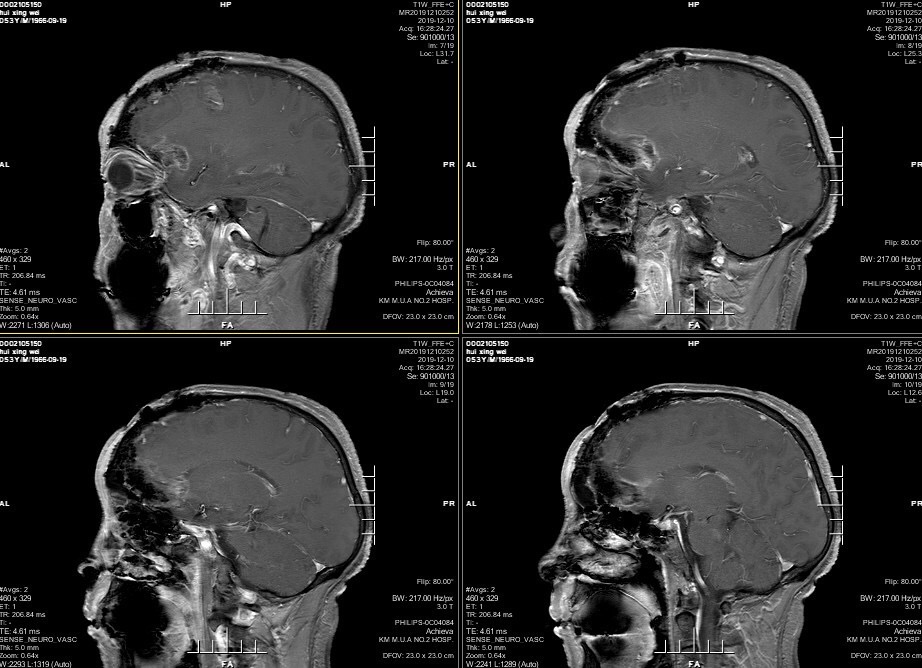

男性患者,53岁,主诉:反复头痛伴恶心一周,突发意识丧失一次。入院查体:神经体统无阳性体征。入院头颅MRI:左额叶胼胝体区囊实性占位,不均匀强化,考虑高级别胶质瘤;长程视频脑电监测提示左侧中央区、顶区、后颞区见中等量低-中-高波幅痫样放电。术前诊断:1.左额叶胼胝体区占位病变;2.继发性癫痫,入院给予降颅压及抗癫痫处理,积极完善术前准备后于2019年12月3日全麻下完成手术,术中行B超引导下切除肿瘤。术后患者无肢体功能及语言功能障碍,复查头颅核磁肿瘤全切,一周后出院开始放化疗治疗。

肿瘤为囊实性。

双侧大脑前动脉受肿瘤推挤。

增强后不均匀强化。